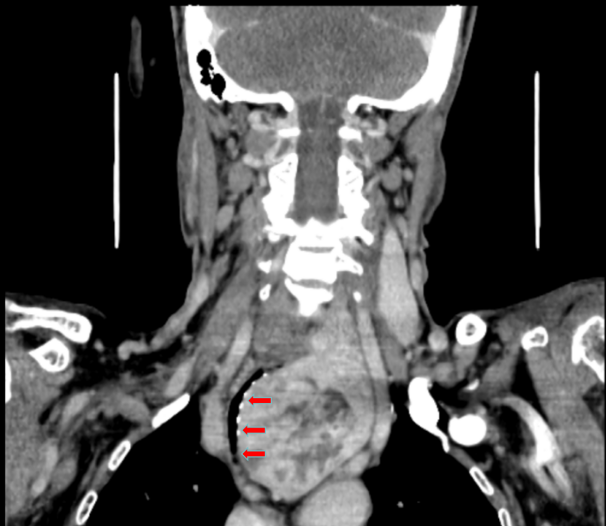

11年前的一次体检,王女士便知甲状腺有肿物,因不痛不痒从未处理。直至近期出现严重呼吸困难、夜间无法平卧,检查才发现肿瘤已沿气管坠入胸腔深处,紧贴主动脉弓。气管最窄处仅剩5毫米,随时可能窒息。

术前CT显示,气管最窄处仅5mm,形似“吸管”